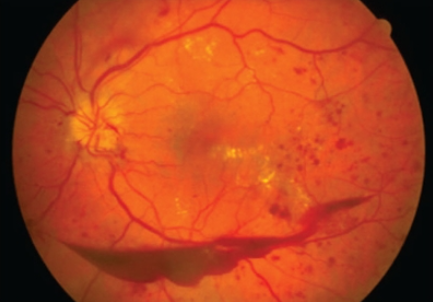

망막에는 수많은 미세혈관과 시신경조직이 복잡하게 얽혀있는데 혈당이 높아지는 당뇨환자의 경우 망막의 미세혈관에 자극과 손상을 줘 종국엔 당뇨망막병증을 유발합니다.

특히 망막은 혈액공급이 아주 중요한 부위로 혈액순환장애는 망막기능에 큰 타격을 줍니다.

당뇨망막병증은 배경성과 증식성으로 구분되며 증식성은 모세혈관, 소동맥, 소정맥 병변을 동반합니다.

보통 출혈은 망막 안이나 앞 어디든 나타나 나룻배 모양, 점 모양 등이 나타날 수 있으며 황반에 침범하면 시력손상 및 실명이 됩니다.